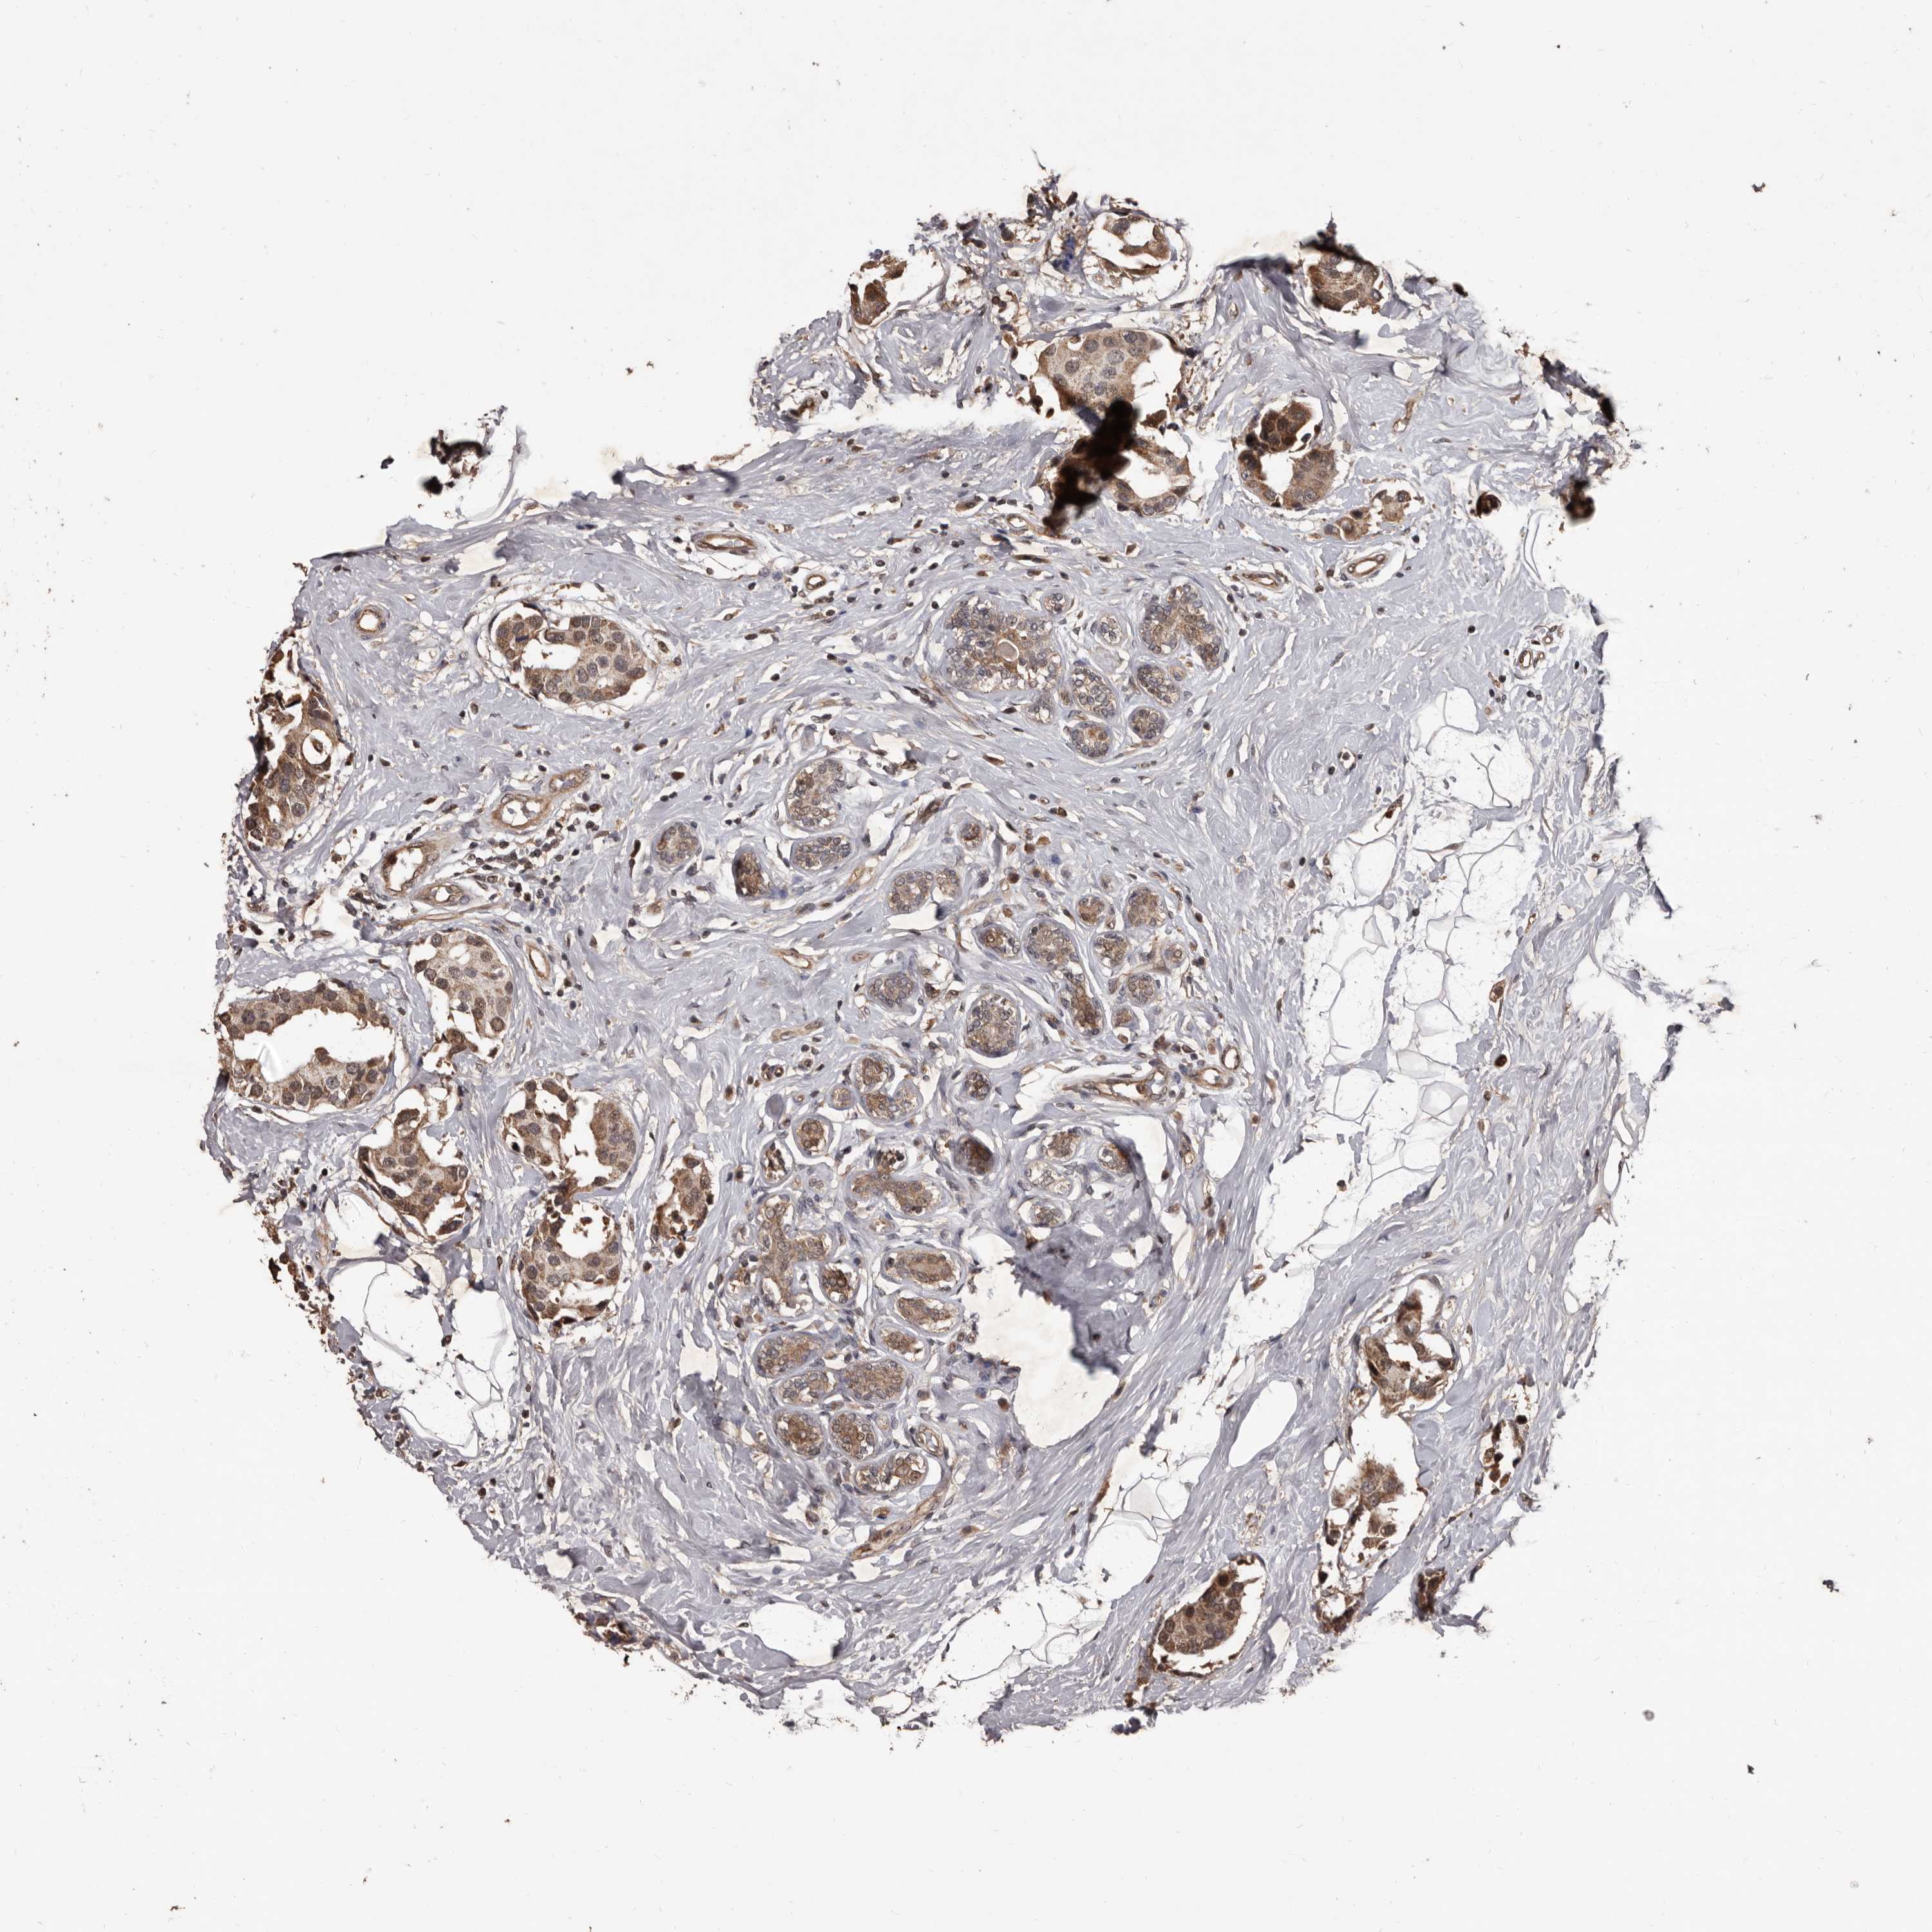

BRCA TCGA BRCA VALIDATION PROTEIN EXPRESSION

ANTIBODIES

AND

VALIDATION